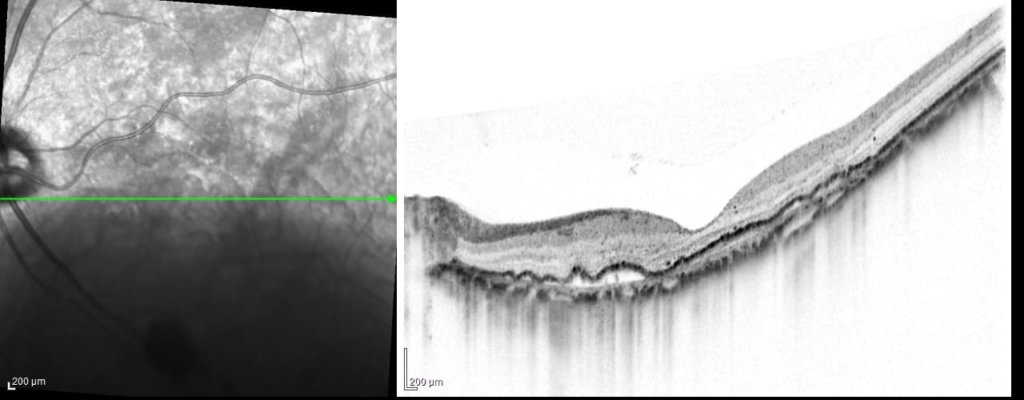

乳頭が下鼻側に傾斜し、下方に萎縮(PPA)がみられる。

両眼ともに、後部ぶどう腫staphylomaの上縁に一致して乳頭下縁から黄斑を横断するように帯状の網脈絡膜の萎縮巣がみられる。また後部ぶどう腫領域に一致して網膜・脈絡膜が菲薄化しているため、紋理眼底tessel lated fundusがみられる。

後部ぶどう腫の上縁に漿液性網膜剥離(SRD)がみられる。この後部ぶどう腫と正常部の境界付近に脈絡膜新生血管の発生を見ることもあるため、注意が必要。